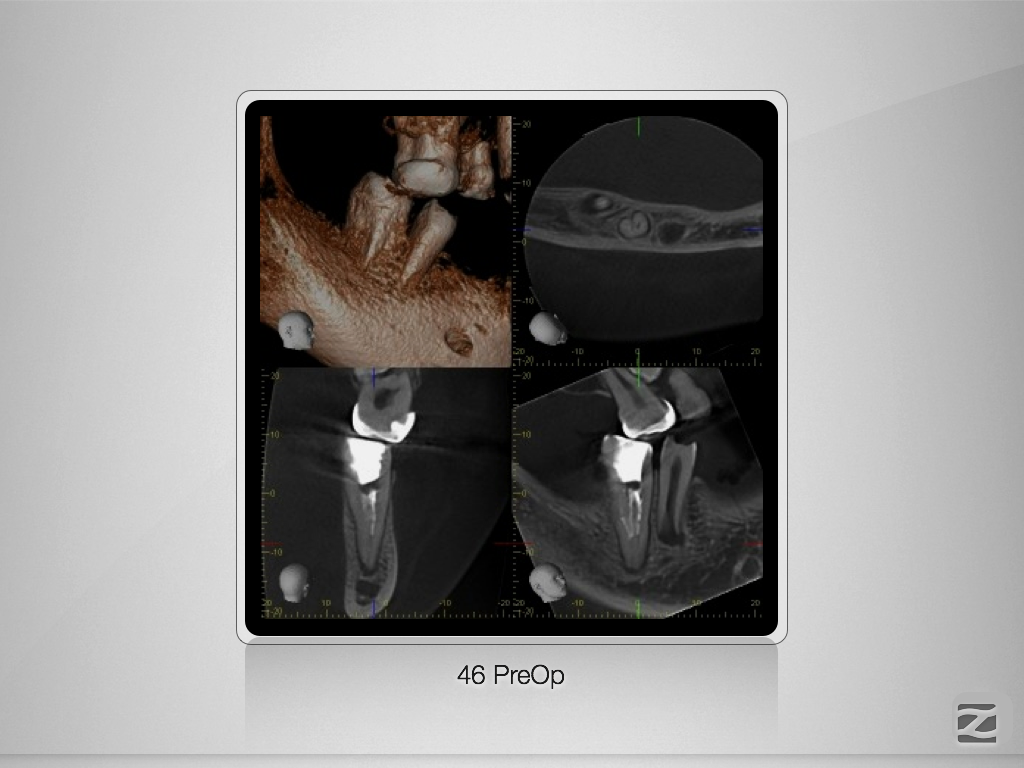

46D.006

Doppeltes C